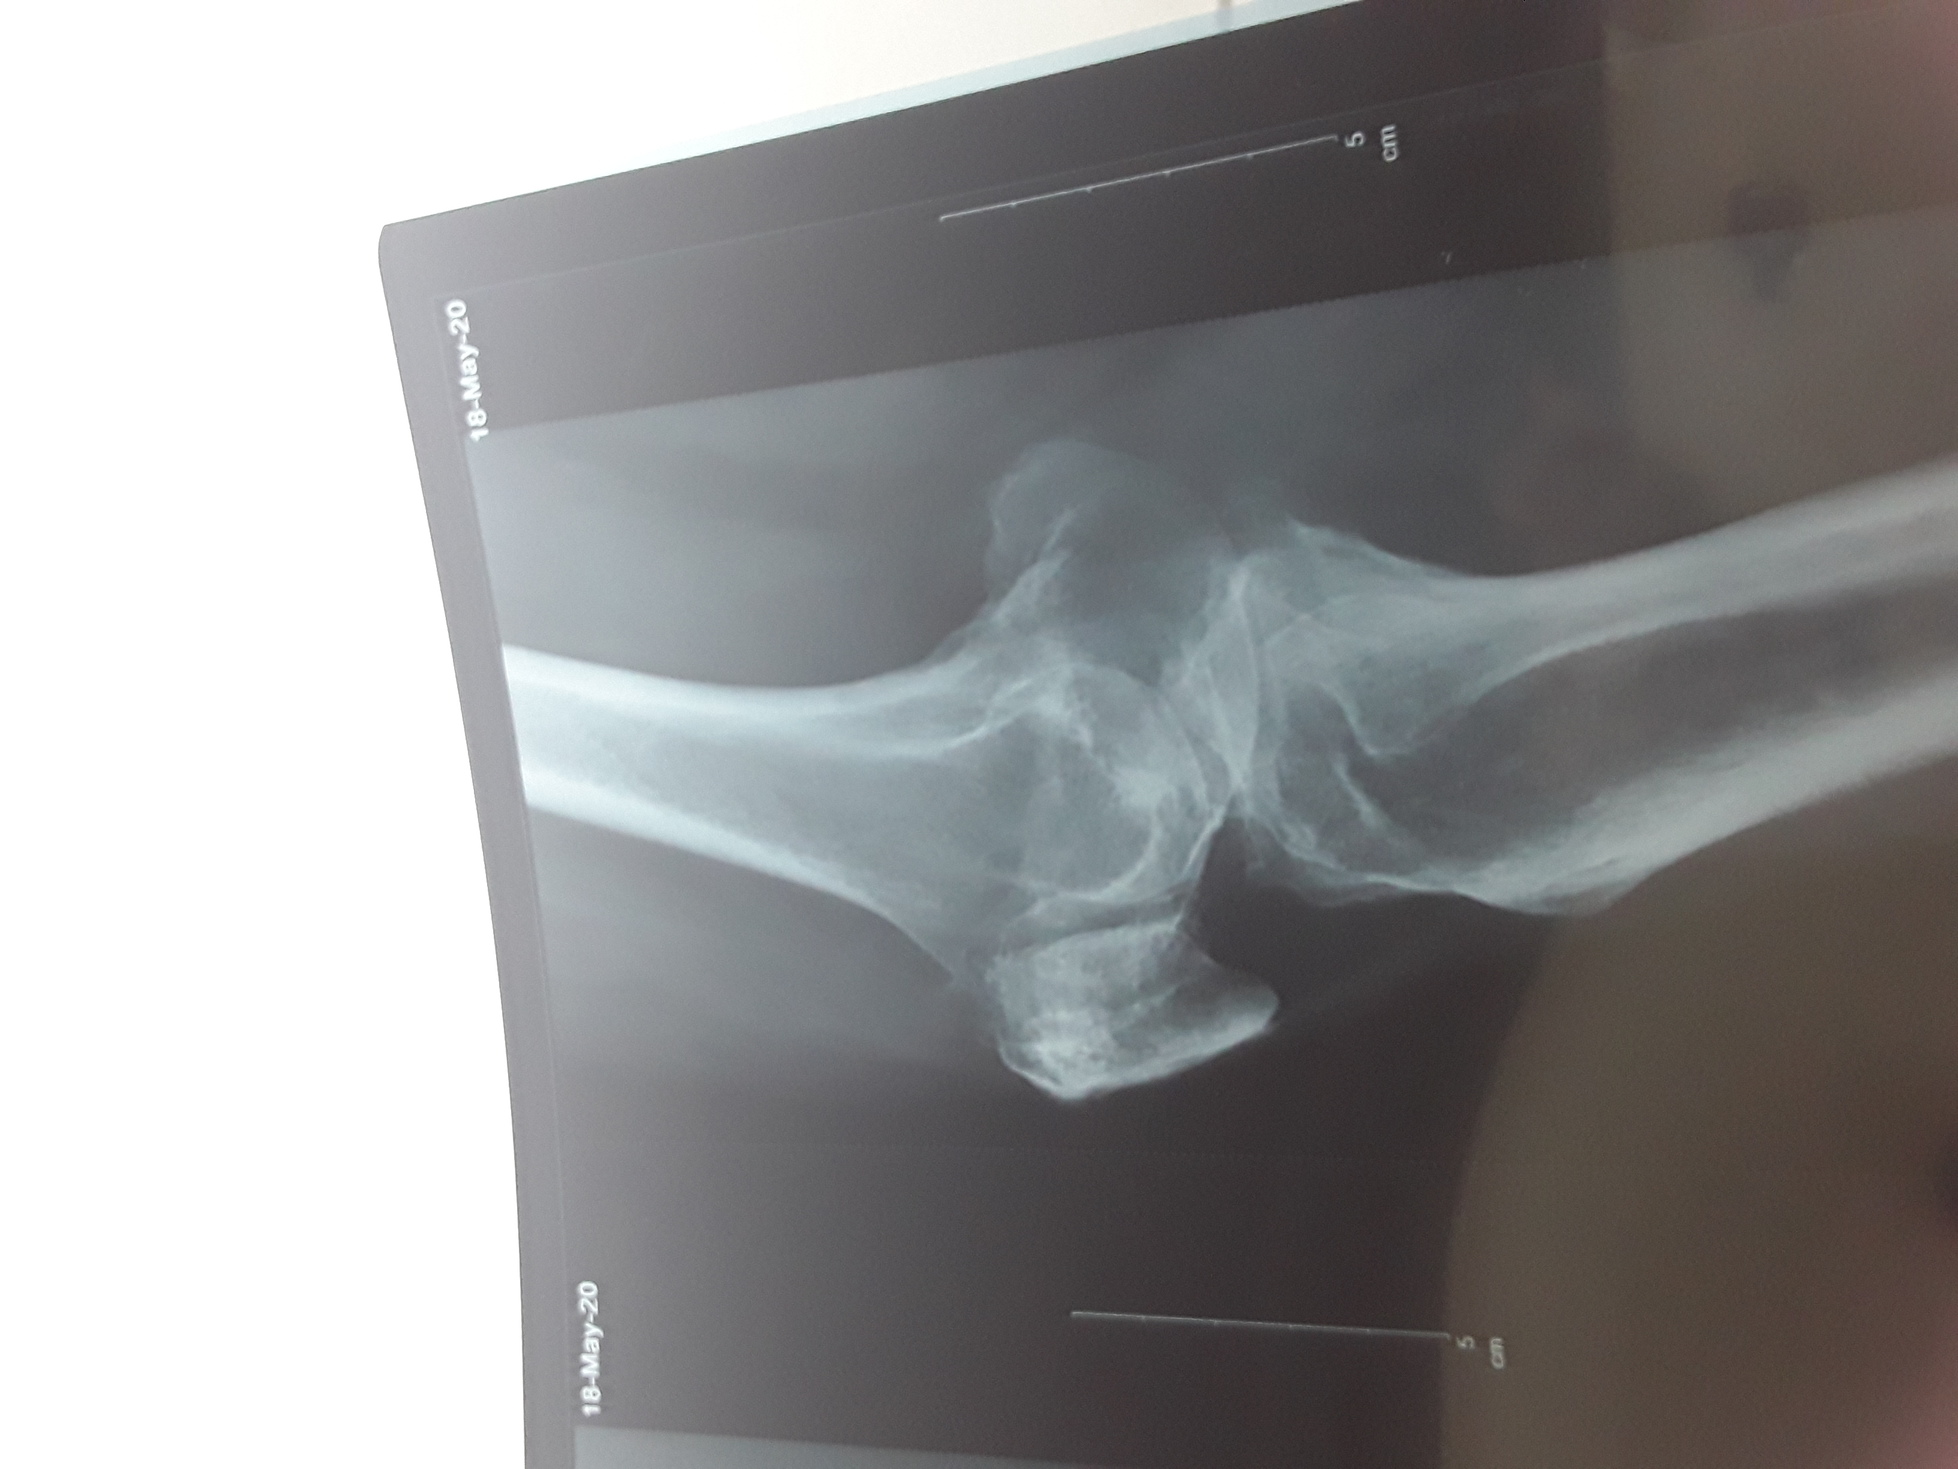

My mother has a histroy of ghout and osteoarthritis. But she is doing all chores without any support . Yetserday, she fell and her knee probably twisted . We take her to emergency ,got the x ray are given but still her knee and leg is not bearing weight. X ray are attached for opinion , is there is something to worry.

Your mom has suffering from advanced OA KNEE. IT require knee replacement surgery. During fall she probably had damaged soft tissue of the knee joint leading to swelling. At this stage please consult a nearest Rheumatologist or orthopedist for intra articular injection.